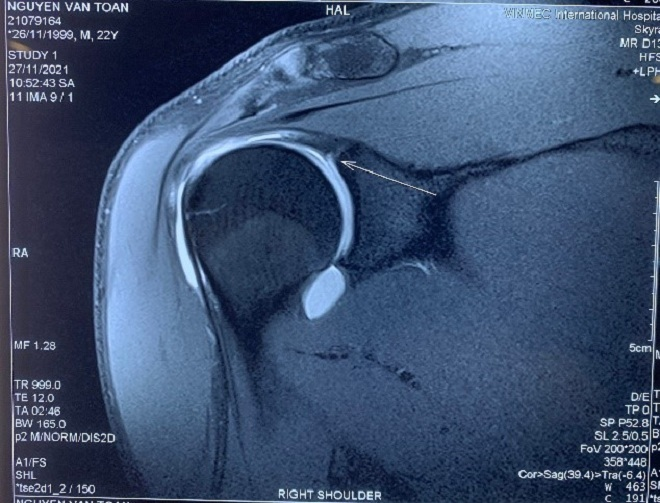

Các bác sĩ cho rằng khả năng đây là tổn thương SLAP vai phải - thương tổn có cơ chế là lực truyền từ cánh tay qua khớp vai đang bị rách, bong khớp, rất phù hợp với kiểu vận động cánh tay đặc thù của thủ môn. Qua phim chụp MRI cản quang và thăm khám lâm sàng, GS Dũng cùng các bác sĩ đã đưa ra kết luận Văn Toản bị chấn thương cơ nhị đầu, cụ thể là bị tổn thương một phần chân bám của cơ nhị đầu cũng như sụn viền chỗ chảo khớp vai.

Phim MRI khi có tiêm thuốc thấy rõ tổn thương hơn.